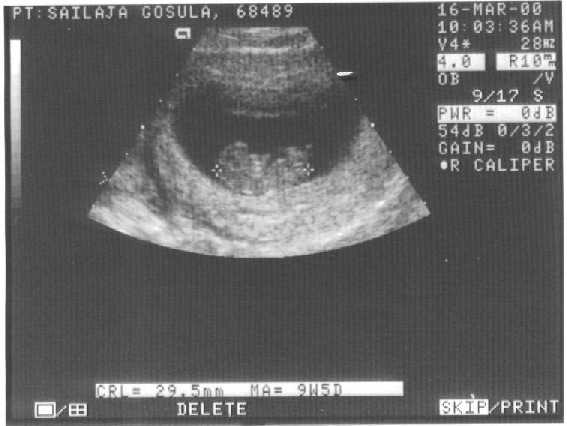

B10weeks.jpg